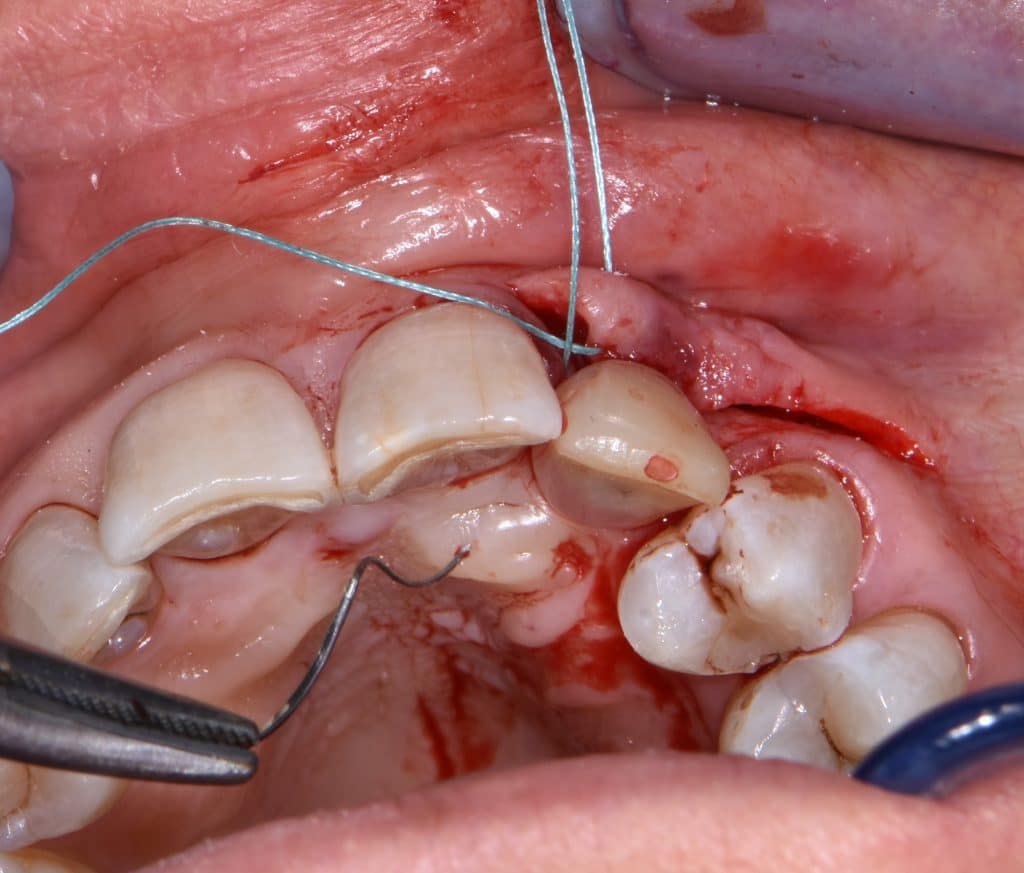

La pz N.G. di anni 52 (ASA 1) viene visitata nel mese di settembre 2017 per la mobilità ed inestetismo dell’elemento protesico 22, (foto iniziali sequenza 1) si evidenzia una frattura parziale della radice, si decide per l’estrazione ( foto sequenza 2) e sostituzione dell’elemento con un restauro implanto-protesico. Purtroppo la scarsa quota ossea apicale all’alveolo post-estrattivo (foto 2 rx) e l’alta valenza estetica dell’elemento ci rende cauti e si programma una socket preservation post estrattiva con l’ausilio delle membrane di prf (foto prf e socket sequenza 3 e 4). Durente i 5 mesi di guarigione la pz porta una protesi parziale mobile (foto 5,2) , a guarigione del sito post estrattivo si evidenzia una buona conservazione dei volumi osseo-gengivali,(foto guarigione sequenza 6) se pur presente una recessione distale all’elemnto 21.Nel mese di febbraio 2018 si procede all’inserimento di un impianto max-stability 3,75x12mm disegnando un lembo anticipato palatino per consentire un aumento dei tessuti vestibolari suturando con tecnica rool flap e trasformando l’elemento parziale mobile in una corona singola a carico immediato sul moncone temporameo applicando i concetti protesici bopt , (foto impianto moncone protesi provvisoria sequenza foto 7-8-9). Durante il periodo di maturazione dei tessuti molli vengono apportate opportune modifiche ai profili del provvisorio al fine di dare maggior spazio al tessuto gengivale, ( fotosequenza 10).Dopo circa 2 mesi dal protesizzazione provvisoria si è proceduto alla realizzazione del manufatto protesico con tecnica chair side sirona con l’ausilio del t-base (foto sequenza 11-12-13), realizzando in una sola seduta una corona in disilicato, ottenendo un risultato più che soddisfacente (Foto 14). Nel controllo a 3 mesi dal carico definitivo si apprezza la perfetta conservazione dei livelli ossei e gengivali. (foto sequenza 15).concludo con un follow up a 18 . Tengo a sottolineare che un caso come questo è stato conducibile con buoni risultati solo grazie alla piena fiducia della pz e alla sua massima motivazione e collaborazione. Ad oggi la pz sorride soddisfatta del risultato. E questo rappresenta la massima ricompensa di chi dedica tutto se stesso alla professione.